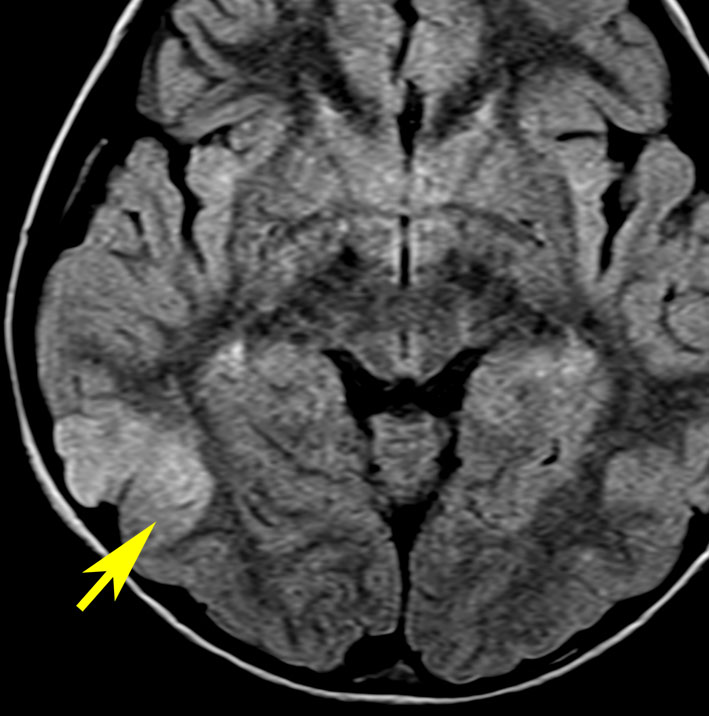

新生児期にてんかん発症した例 focal cortical dysplasia 2b

右頭頂葉の皮質異形成です。生後2週間目に両上肢を挙げるような発作を生じて難治化,1歳を超える頃には発達の遅れが目立ちました。新生児期にはMRIで描出できなかった病変が1歳になって初めて写るようになりました。手術で病変摘出 lesionectomy して投薬中断ができて,その後は普通に育ちました。